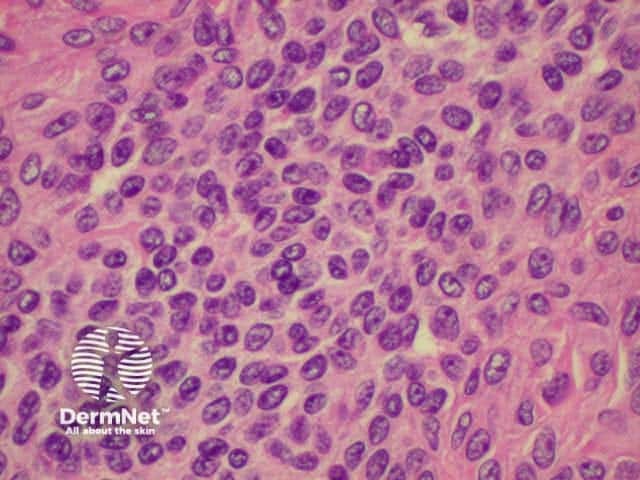

Histology is shown below.

Histology of intradermal naevus Superficial epithelioid naevus cells Deeper small dark naevus cells